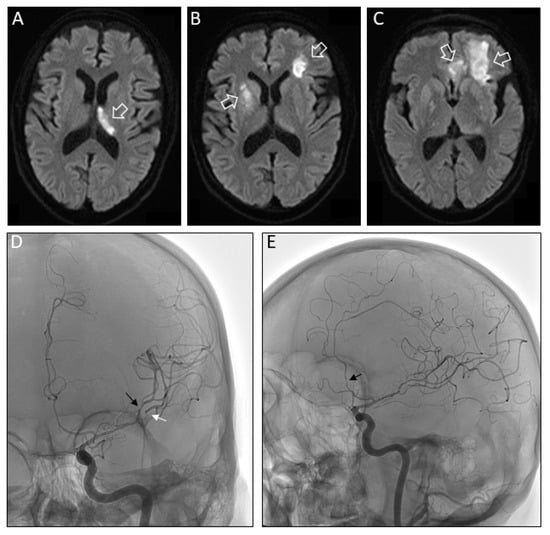

Brain magnetic resonance imaging (MRI) disclosed a recent infarction of the left thalamus (Figure 2A). We observed new neurological symptoms over the next days with weakness and numbness on the left side, fluctuating cognitive function, mood and behavior. Brain MRI on day 7 from readmission showed further new ischemic lesions in the previously affected as well as additional vascular territories (Figure 2B,C). Conventional angiography revealed narrowing of intracerebral cerebral vessels consistent with vasculitis. The abnormalities were most prominent in the M2 segments of the left medial and the anterior cerebral artery (Figure 2D,E). High dose methylprednisolone (1g per day) was added for 7 days and acetylsalicylic acid switched to clopidogrel. There was no evidence for cardiac arrhythmia on Holter-ECG or cardiac thrombus or endocarditis on echocardiography. Yet, clinical deterioration was not halted and the patient died one month later in a palliative care setting. The approval by the local ethics committee is on file (415-EP/73/748-2017).

Figure 2.

(A) Fluid attenuated inversion recovery (FLAIR) MR axial images of the brain on second admission reveals acute infarction in the region of the left thalamus (white open arrow). (B) Seven days later additional FLAIR hyperintensities consistent with brain infarction were present in the region of the right putamen and in left juxtacortical frontal lobe (white open arrows). (C) The previous infarction also extended further rostral and affected white matter and U-fibers in the left frontal lobe and a portion of the left cingulate gyrus (white open arrows). (D) Anterior-posterior projection of early arterial phase of digital subtraction angiography (DSA) after selective left internal carotid catheterization showing multifocal segmental narrowing in the left superior (black arrow) and inferior (white arrow) M2 segments of the middle cerebral artery. Lateral DSA projection showing narrowing in left anterior cerebral artery (Panel E).